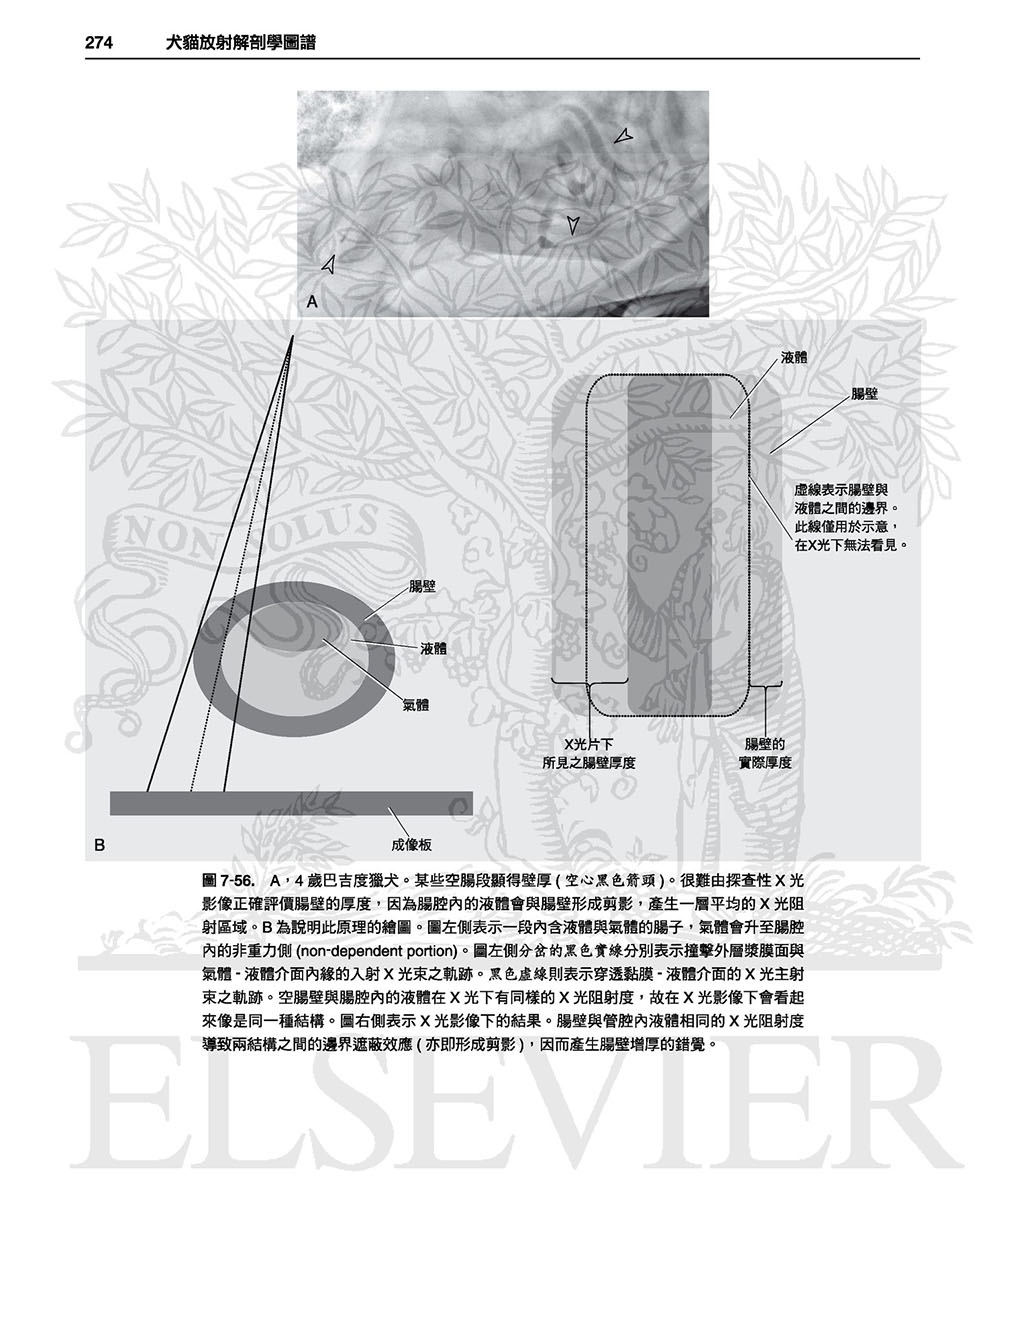

本書並不只是單純的圖譜,各身體部位皆有文字敘述,

因此有助於讀者理解各構造於X光影像學中如此呈現之原因,且提供了讀者對於X光影像學原理基礎性的理解,

有助於對其他正常變異之辨別,雖然可能需要讀者花點心力與圖譜對比使用,但對於判讀能力會有不小的幫助。(本書前言)

以這本詳盡的圖譜學習犬貓正常放射線解剖學的範圍。精通本書將可使診斷更精確並達到更佳的治療效果!

全書皆為高對比的數位影像,除提供正常影像的深入判讀外,亦提供常見且易被誤判為疾病的正常變異;另外並提供多張電腦斷層影像以強調某些結構之影像在放射線學下顯得如此獨特的原因。

本書不但含有豐富圖片,身體各部份皆附上文字描述以協助讀者了解放射解剖學原則,讀者可舉一反三、甚至能以此理解未包含於本書的正常變異。

.詳盡的文字說明及圖片標示

.未標記的原始圖片及標示後的圖片比對

最後,本書並不只是單純的圖譜,各身體部位皆有文字描述,因此有助於讀者 理解各構造於X光影像學中如此呈現之原因,且提供了讀者對於X光影像學原理基礎性的理解,有助於對其他正常變異之辨別,雖然可能需要讀者花點心力與圖譜對比使用,但對於判讀能力會有不小的幫助。

全書皆為高對比的數位影像,除提供正常影像的深入判讀外,亦提供常見且易被誤判為疾病的正常變異;另外並提供多張電腦斷層影像以強調某些結構之影像在放射線學下顯得如此獨特的原因。

本書不但含有豐富圖片,身體各部份皆附上文字描述以協助讀者了解放射解剖學原則,讀者可舉一反三、甚至能以此理解未包含於本書的正常變異。

.詳盡的文字說明及圖片標示

.未標記的原始圖片及標示後的圖片比對

最後,本書並不只是單純的圖譜,各身體部位皆有文字描述,因此有助於讀者 理解各構造於X光影像學中如此呈現之原因,且提供了讀者對於X光影像學原理基礎性的理解,有助於對其他正常變異之辨別,雖然可能需要讀者花點心力與圖譜對比使用,但對於判讀能力會有不小的幫助。